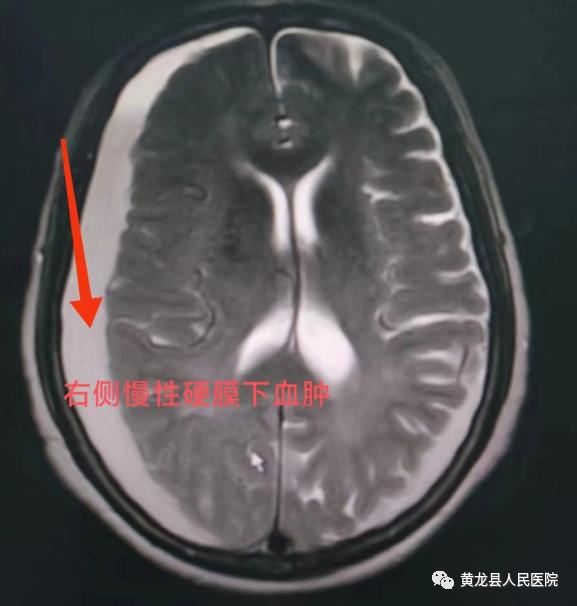

术前颅脑MRI 、术后颅脑CT

78岁的女性患者,既往体质一般。入院1月前,因外伤导致跌倒,未给予任何处理,4天前,出现头痛、头晕,肢体活动受限,伴有恶心、呕吐。家属急送至我院急诊科就诊,行颅脑CT示:双侧硬膜下血肿(脑实质内出血量约100ml)。诊断:双侧慢性硬膜下血肿,立即给予脱水降颅压、止血等相应治疗。